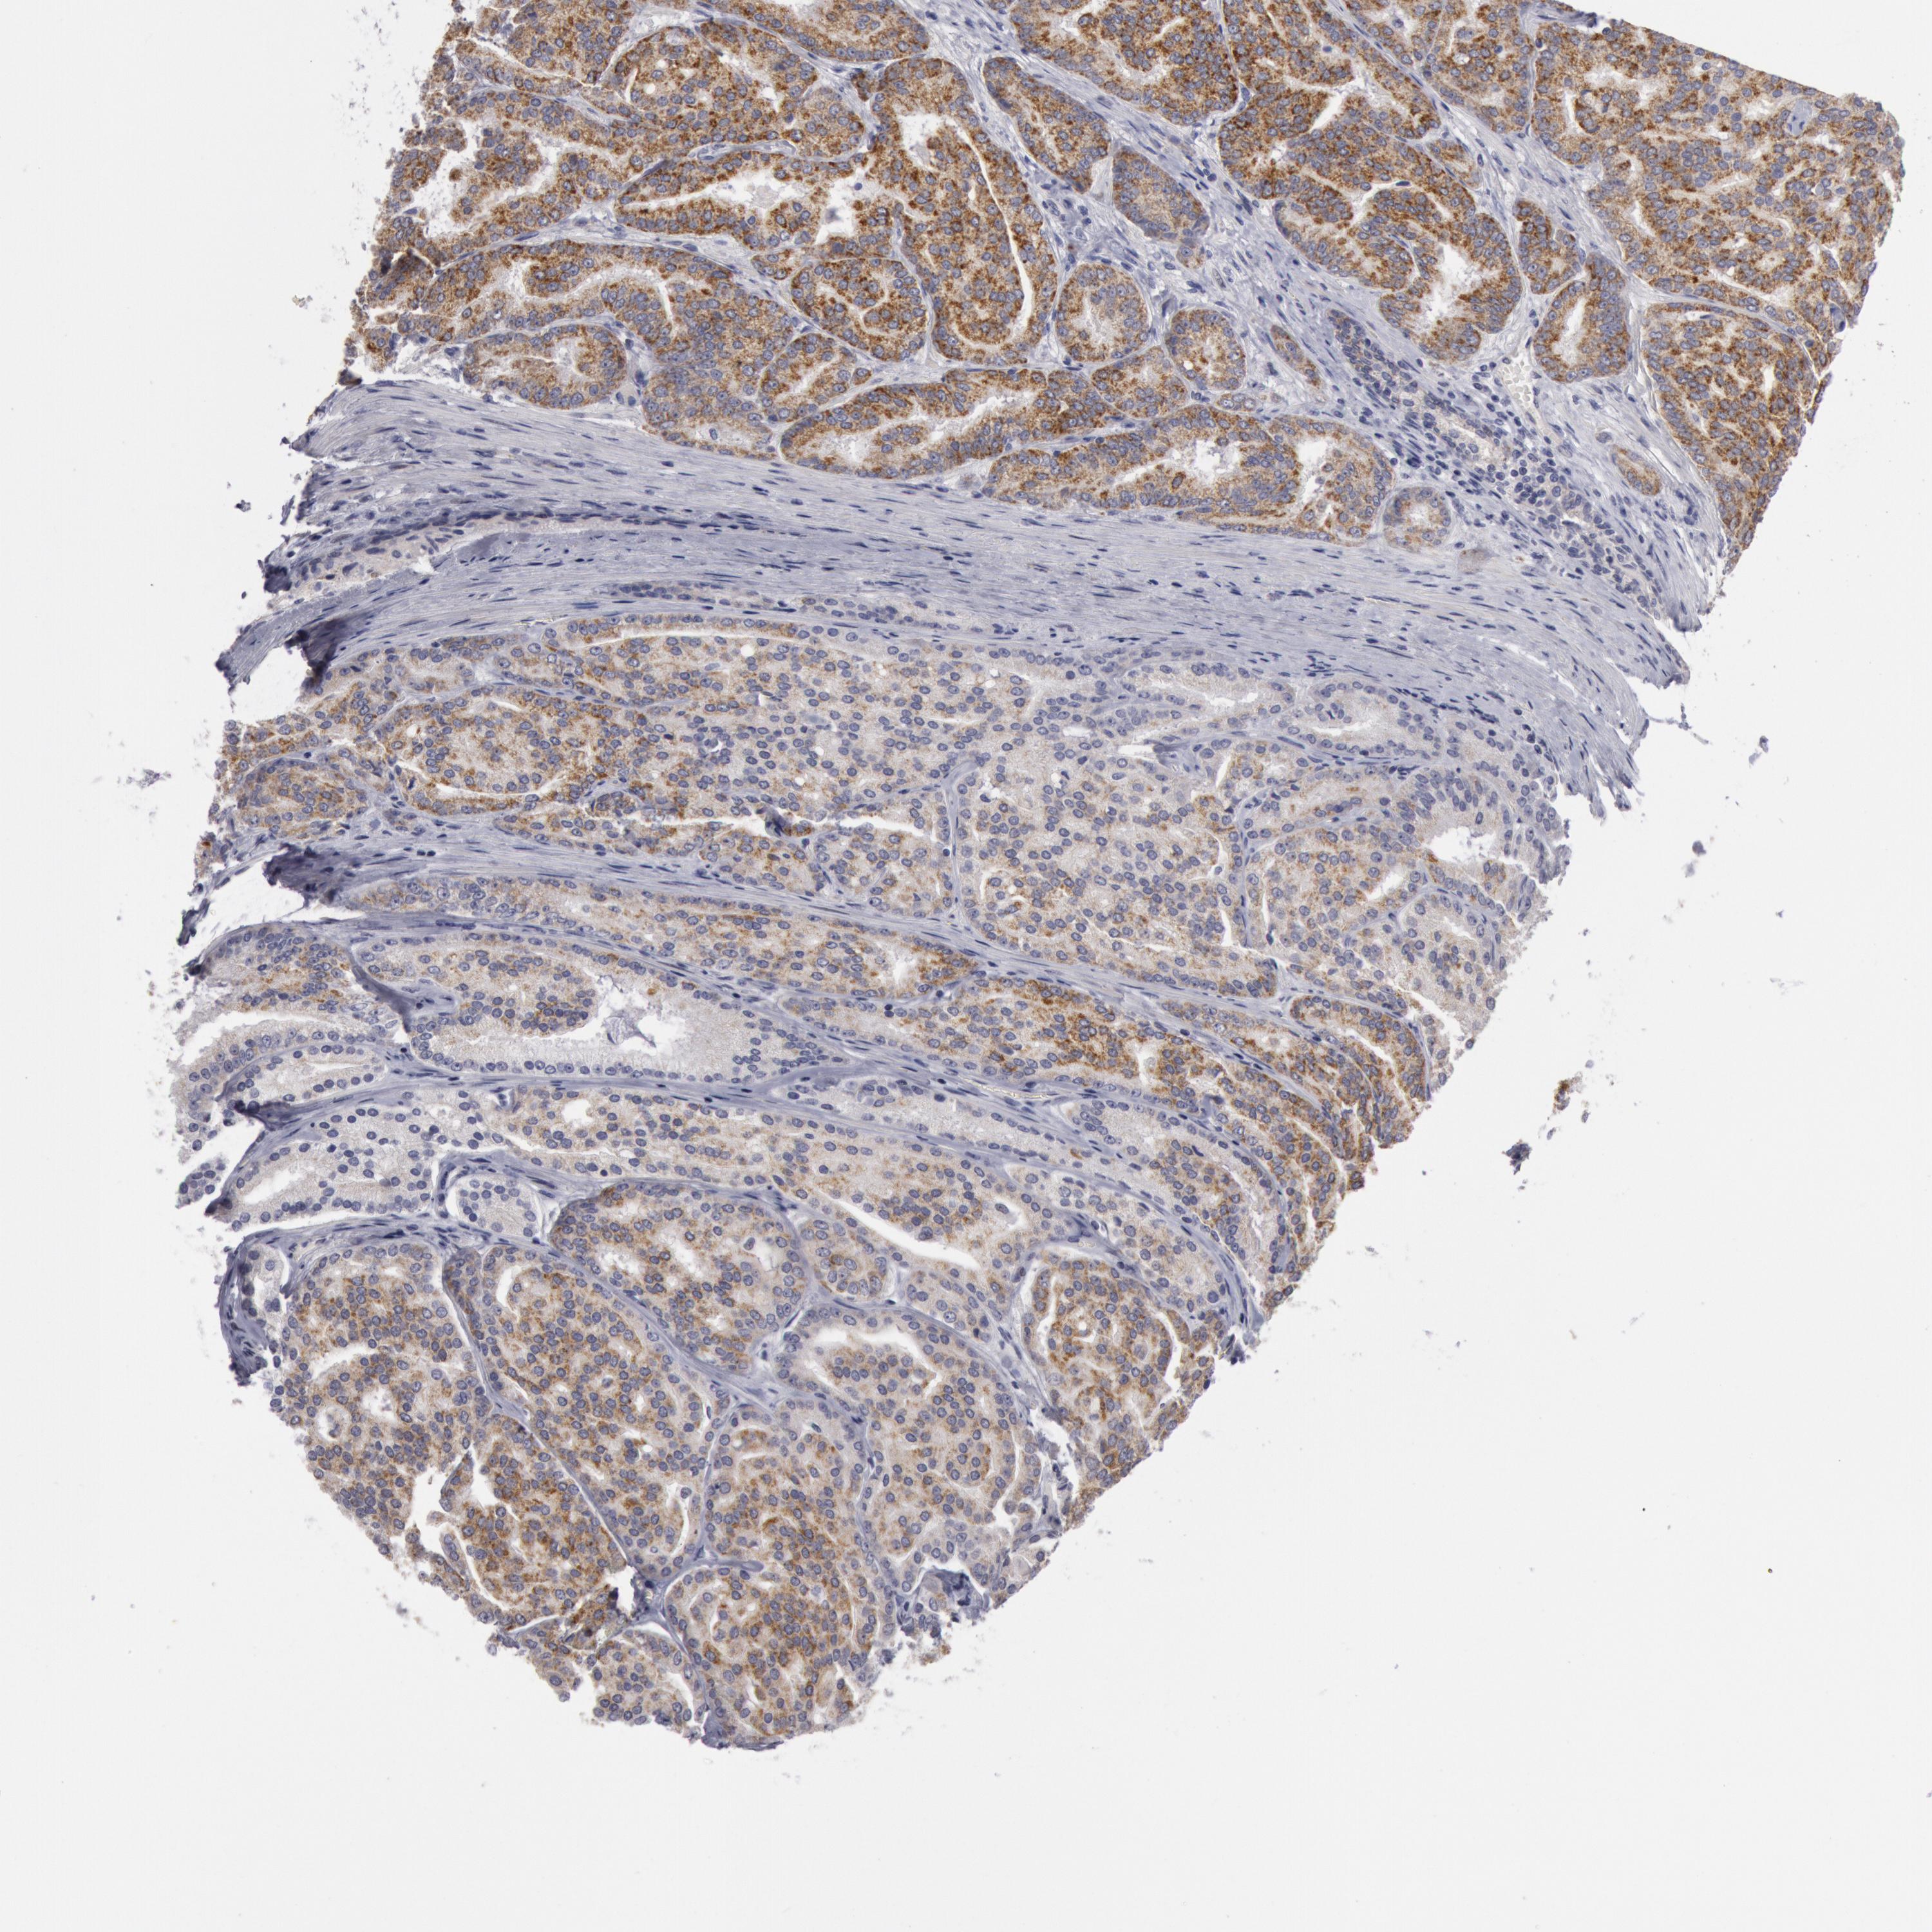

PROSTATE CANCER - Protein expressioni

A mouse-over function shows sample information and annotation data. Click on an image to view it in a full screen mode. Samples can be filtered based on level of antibody staining by selecting one or several of the following categories: high, medium, low and not detected. The assay and annotation is described here.

Note that samples used for immunohistochemistry by the Human Protein Atlas do not correspond to samples in the TCGA dataset.

Antibody stainingi

Antibody staining in the annotated cell types in the current human tissue is reported as not detected, low, medium, or high, based on conventional immunohistochemistry profiling in selected tissues. This score is based on the combination of the staining intensity and fraction of stained cells.

Each image is clickable and will lead to virtual microscopy that enables deeper exploration of all samples and also displays staining intensity scores, fraction scores and subcellular localization as well as patient and tissue information for each sample.

Antibody HPA001168

Staining

High

Medium

Low

Not detected

Intensity

Strong

Moderate

Weak

Negative

Quantity

>75%

75%-25%

<25%

None

Location

Nuclear

Cytoplasmic/membranous

Cytoplasmic/membranous,nuclear

Adenocarcinoma, Medium grade

Adenocarcinoma, Low grade

Adenocarcinoma, High grade